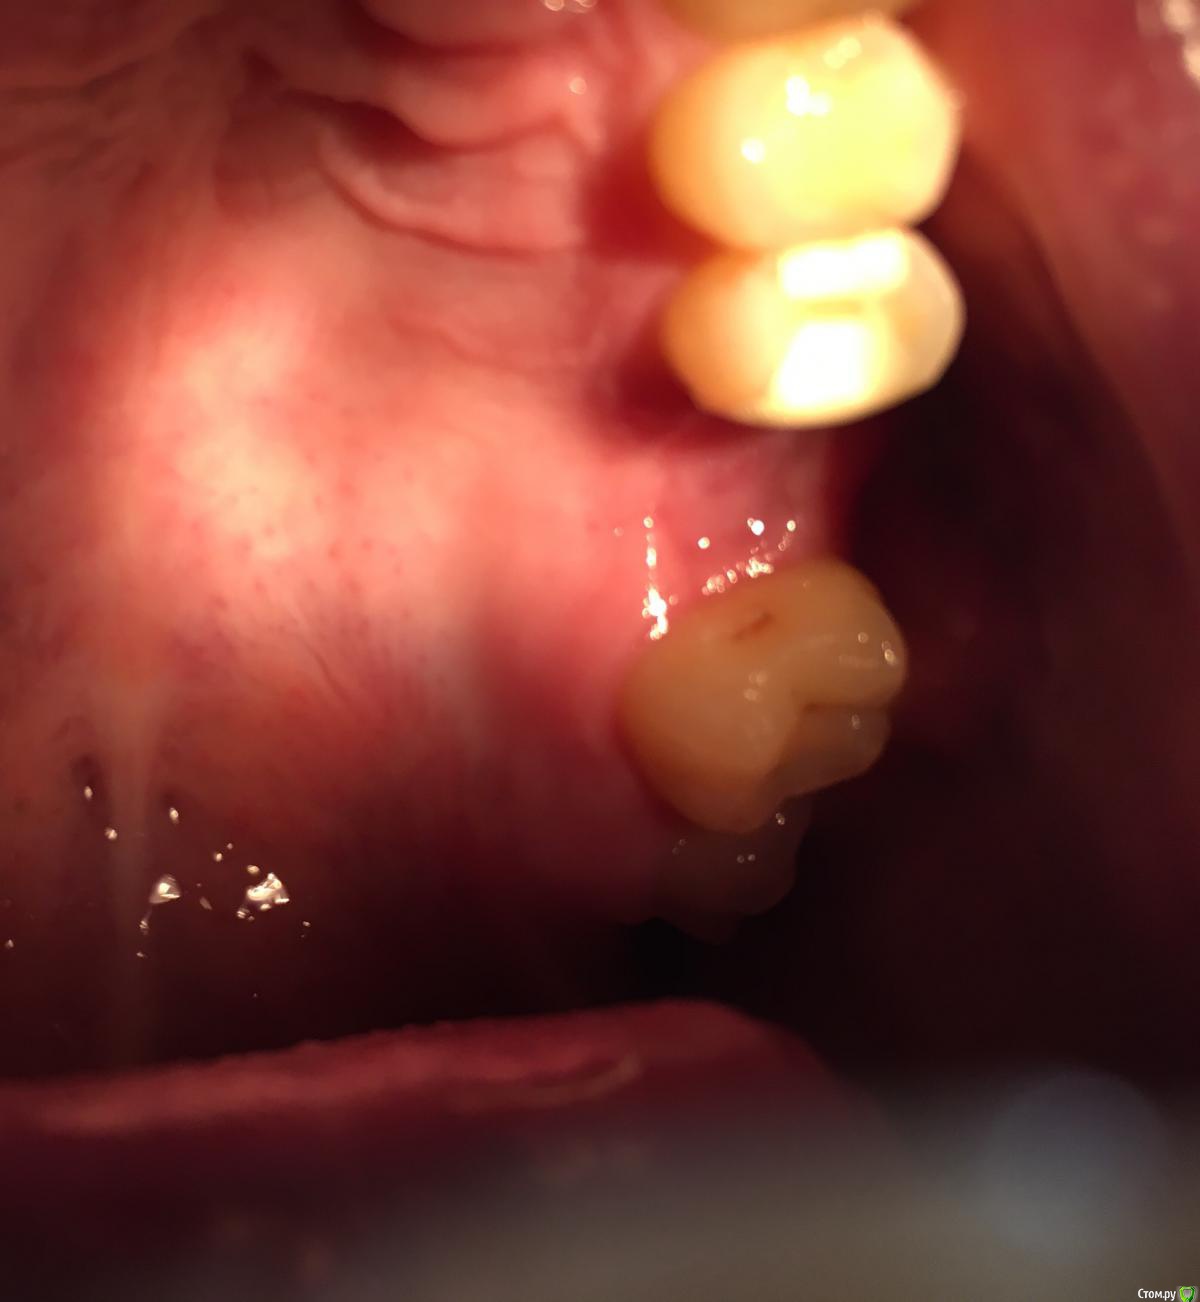

Bier Опубликовано 3 августа, 2018 Поделиться Опубликовано 3 августа, 2018 Точки болеть не могут, трогать их не нужно.Альвеолит может быть. Как лунка то выглядит? 1 Ссылка на комментарий

Павел10538 Опубликовано 3 августа, 2018 Автор Поделиться Опубликовано 3 августа, 2018 . Ссылка на комментарий

Павел10538 Опубликовано 3 августа, 2018 Автор Поделиться Опубликовано 3 августа, 2018 (изменено) Сфотографировал как получилось. Где то внутри какие-то жжения идут. Изменено 3 августа, 2018 пользователем Павел10538 Ссылка на комментарий

Bier Опубликовано 3 августа, 2018 Поделиться Опубликовано 3 августа, 2018 попробуйте небольшое зеркало найти и сфоткать отражение в нем. Вообще лунка вроде выглядит хорошо. 1 Ссылка на комментарий